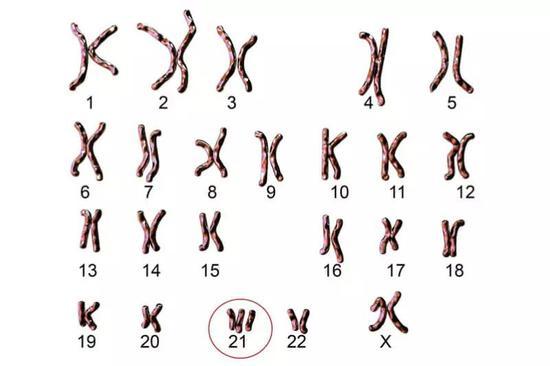

1959年,法国遗传学家杰罗姆·勒琼发现罪魁祸首是人体的染色体变异。

细胞减数分裂*时,第21对染色体因未及时分离而比正常多出一条。

因而在生殖细胞融合后形成的受精卵中异常地存在三条染色体。

这种人们所熟知的致病起因是最常见的一种方式。

约95%的病例是由此造成。

而仍有约5%的小概率是发生了染色体的易位。

通常是21号染色体的部分材料附着在14号染色体上。

因此它也被称为21三体综合征。